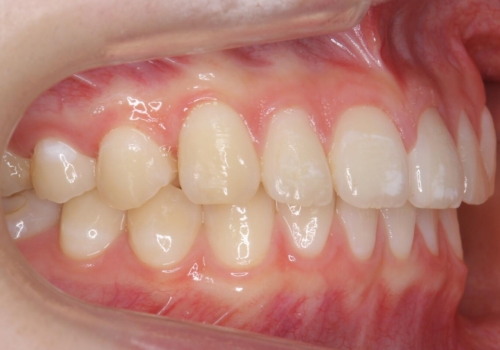

- 前歯のすき間を気にして来院。

全体矯正ではなく部分矯正で治療することになりました。

その代わり、すき間をすべて閉じるのは難しく、両脇の目立たないところに集めて治療終了しています。

低予算、短期間で治療も終了し、大変満足していただきました。

全体矯正をしていないため、就寝時にリテーナー使用は継続していただくことになっています。